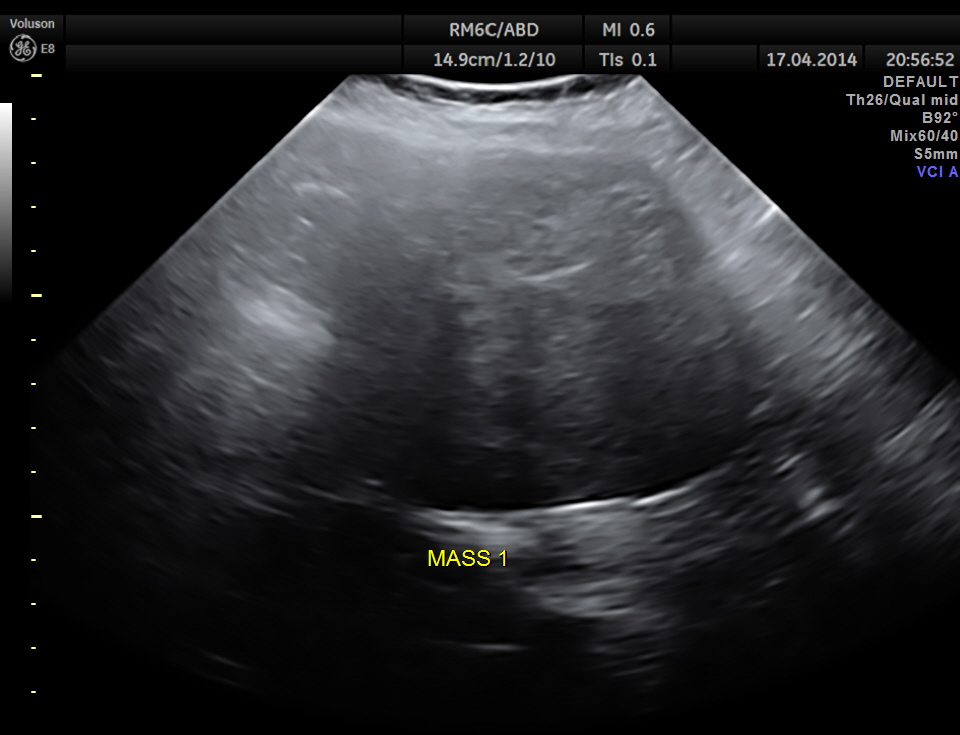

Two distinct mass lesions were seen in the right side of the abdomen in the lumbar and hypochondriac regions . Though they appeared distinct from the liver , it was a bit confusing.

The mass lesions are seen below.

Thw two masses seen out of the uterus and mainly in the right upper quadrant are shown below.

The ultrasound gave us a few inconclusive findings . Uterus was massively enlarged ; a large fibroid was seen ; adenomyosis was seen ; endometrium was thickened ; two large mass lesions were seen in the right upper quadrant and right lumbar region . But it was difficult to ascertain the origin of these extra uterine masses .